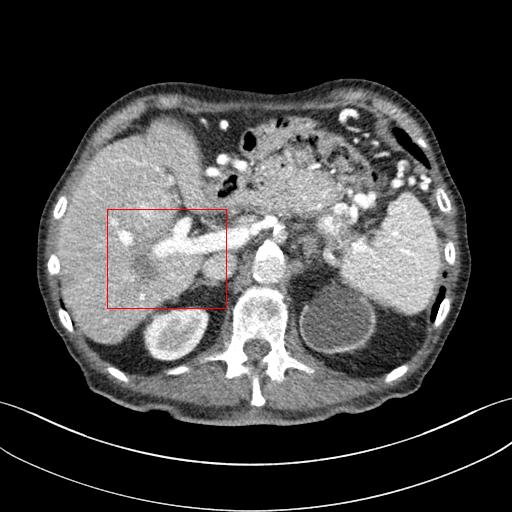

As shown in Table 3, DIP has exhibited the worst performance among all the methods. On the other hand, the ConsensusNet yielded a better FID and TML than BM3D but a lower PSNR and SSIM than other methods. The ConsensusNet divided the original projection data of the low dose CT image into two subgroups and back-projected to create the noisy input signal. Consequently, the noisy input image is much noisier than the original LDCT image. Also, the structural loss occurred during the generation of noisy images, so as a result, the PSNR and SSIM of this method are lower than other methods. Texture matching loss (TML) is used to measure the texture difference between the reconstructed and original images. The lower value of TML indicates that the generated texture is similar to the original. In comparison, FID estimates the distance between the distribution of the generated image and real images. A lower value of FID signifies the generated images are more similar to the original image. The current deep learning era demands a denoised image with a low value of these metrics. These denoised images may be used as input for other image classification tasks or segmentation networks. In this regard, the ConsensusNet is superior to the BM3D because it uses the deep neural network’s expression power. CycleGAN is another powerful unsupervised method for image-to-image translation; it achieved better performance than the other methods. However, CycleGAN has a lot of bottlenecks, e.g., longer training time, computation power, hyper-parameter tuning, etc. All these bottlenecks make CycleGAN ill-suited for practical deployment. Meanwhile, our proposed method has achieved the highest PSNR, SSIM, FID, and VIF among all the other methods. Next, we compare the result of denoising visually in Figure 6. It can be observed that the proposed method performs significantly better than the other unsupervised methods. BM3D output produced a blurry denoised image and contained many splotchy artifacts. The same blurriness can be observed in the output of ConsensusNet, and DIP, although noise suppression is adequate, and splotchy artifact is absent. In the output of CycleGAN, we can observe the presence of residual noise, especially in the high noise regions. Next, we identified one low attenuated lesion in the sample image and marked the lesion with a red colour bounding box. The zoomed view of the region inside the bounding box is given in Figure 7. In our method’s output image, the lesion’s visibility is enhanced significantly than in other methods. Despite being an unsupervised method, the visibility of the lesion is comparable with the original NDCT image. Also, from the zoomed view, we can perceive that our method has suppressed the granular pattern without losing the original image’s texture.

Refer to caption

(a) LDCT

(b) BM3D

(c) DIP

(d) CycleGAN

(e) ConsensusNet

(f) Proposed

(g) NDCT

Figure 7: Comparison of denoising performance of different network. Zoomed view of the region inside the bounding box shown in the images for Figure 6